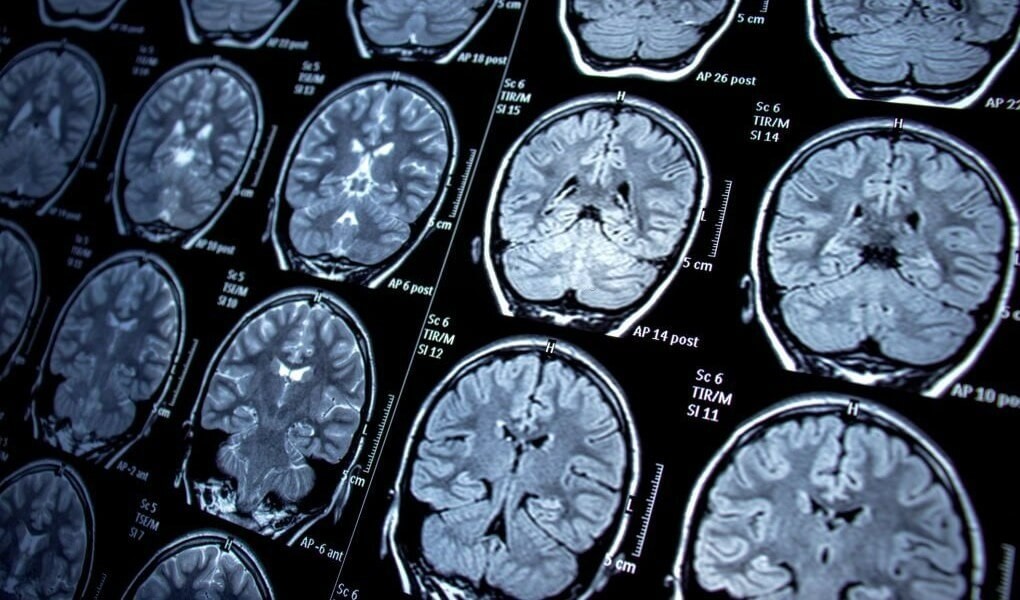

El Parkinson, una enfermedad neurodegenerativa, es un trastorno progresivo del sistema nervioso central. Se origina por la pérdida gradual de neuronas que producen dopamina en la sustancia negra del cerebro. La dopamina es esencial para el control del movimiento, y su disminución da lugar a una variedad de síntomas que impactan profundamente en la vida de quienes lo padecen.

Actualmente, no existe una prueba definitiva para detectar el Parkinson. El diagnóstico se realiza mediante una evaluación clínica detallada por parte de un neurólogo especializado, junto con estudios para descartar otras enfermedades.